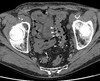

4

5

Perfectly

11